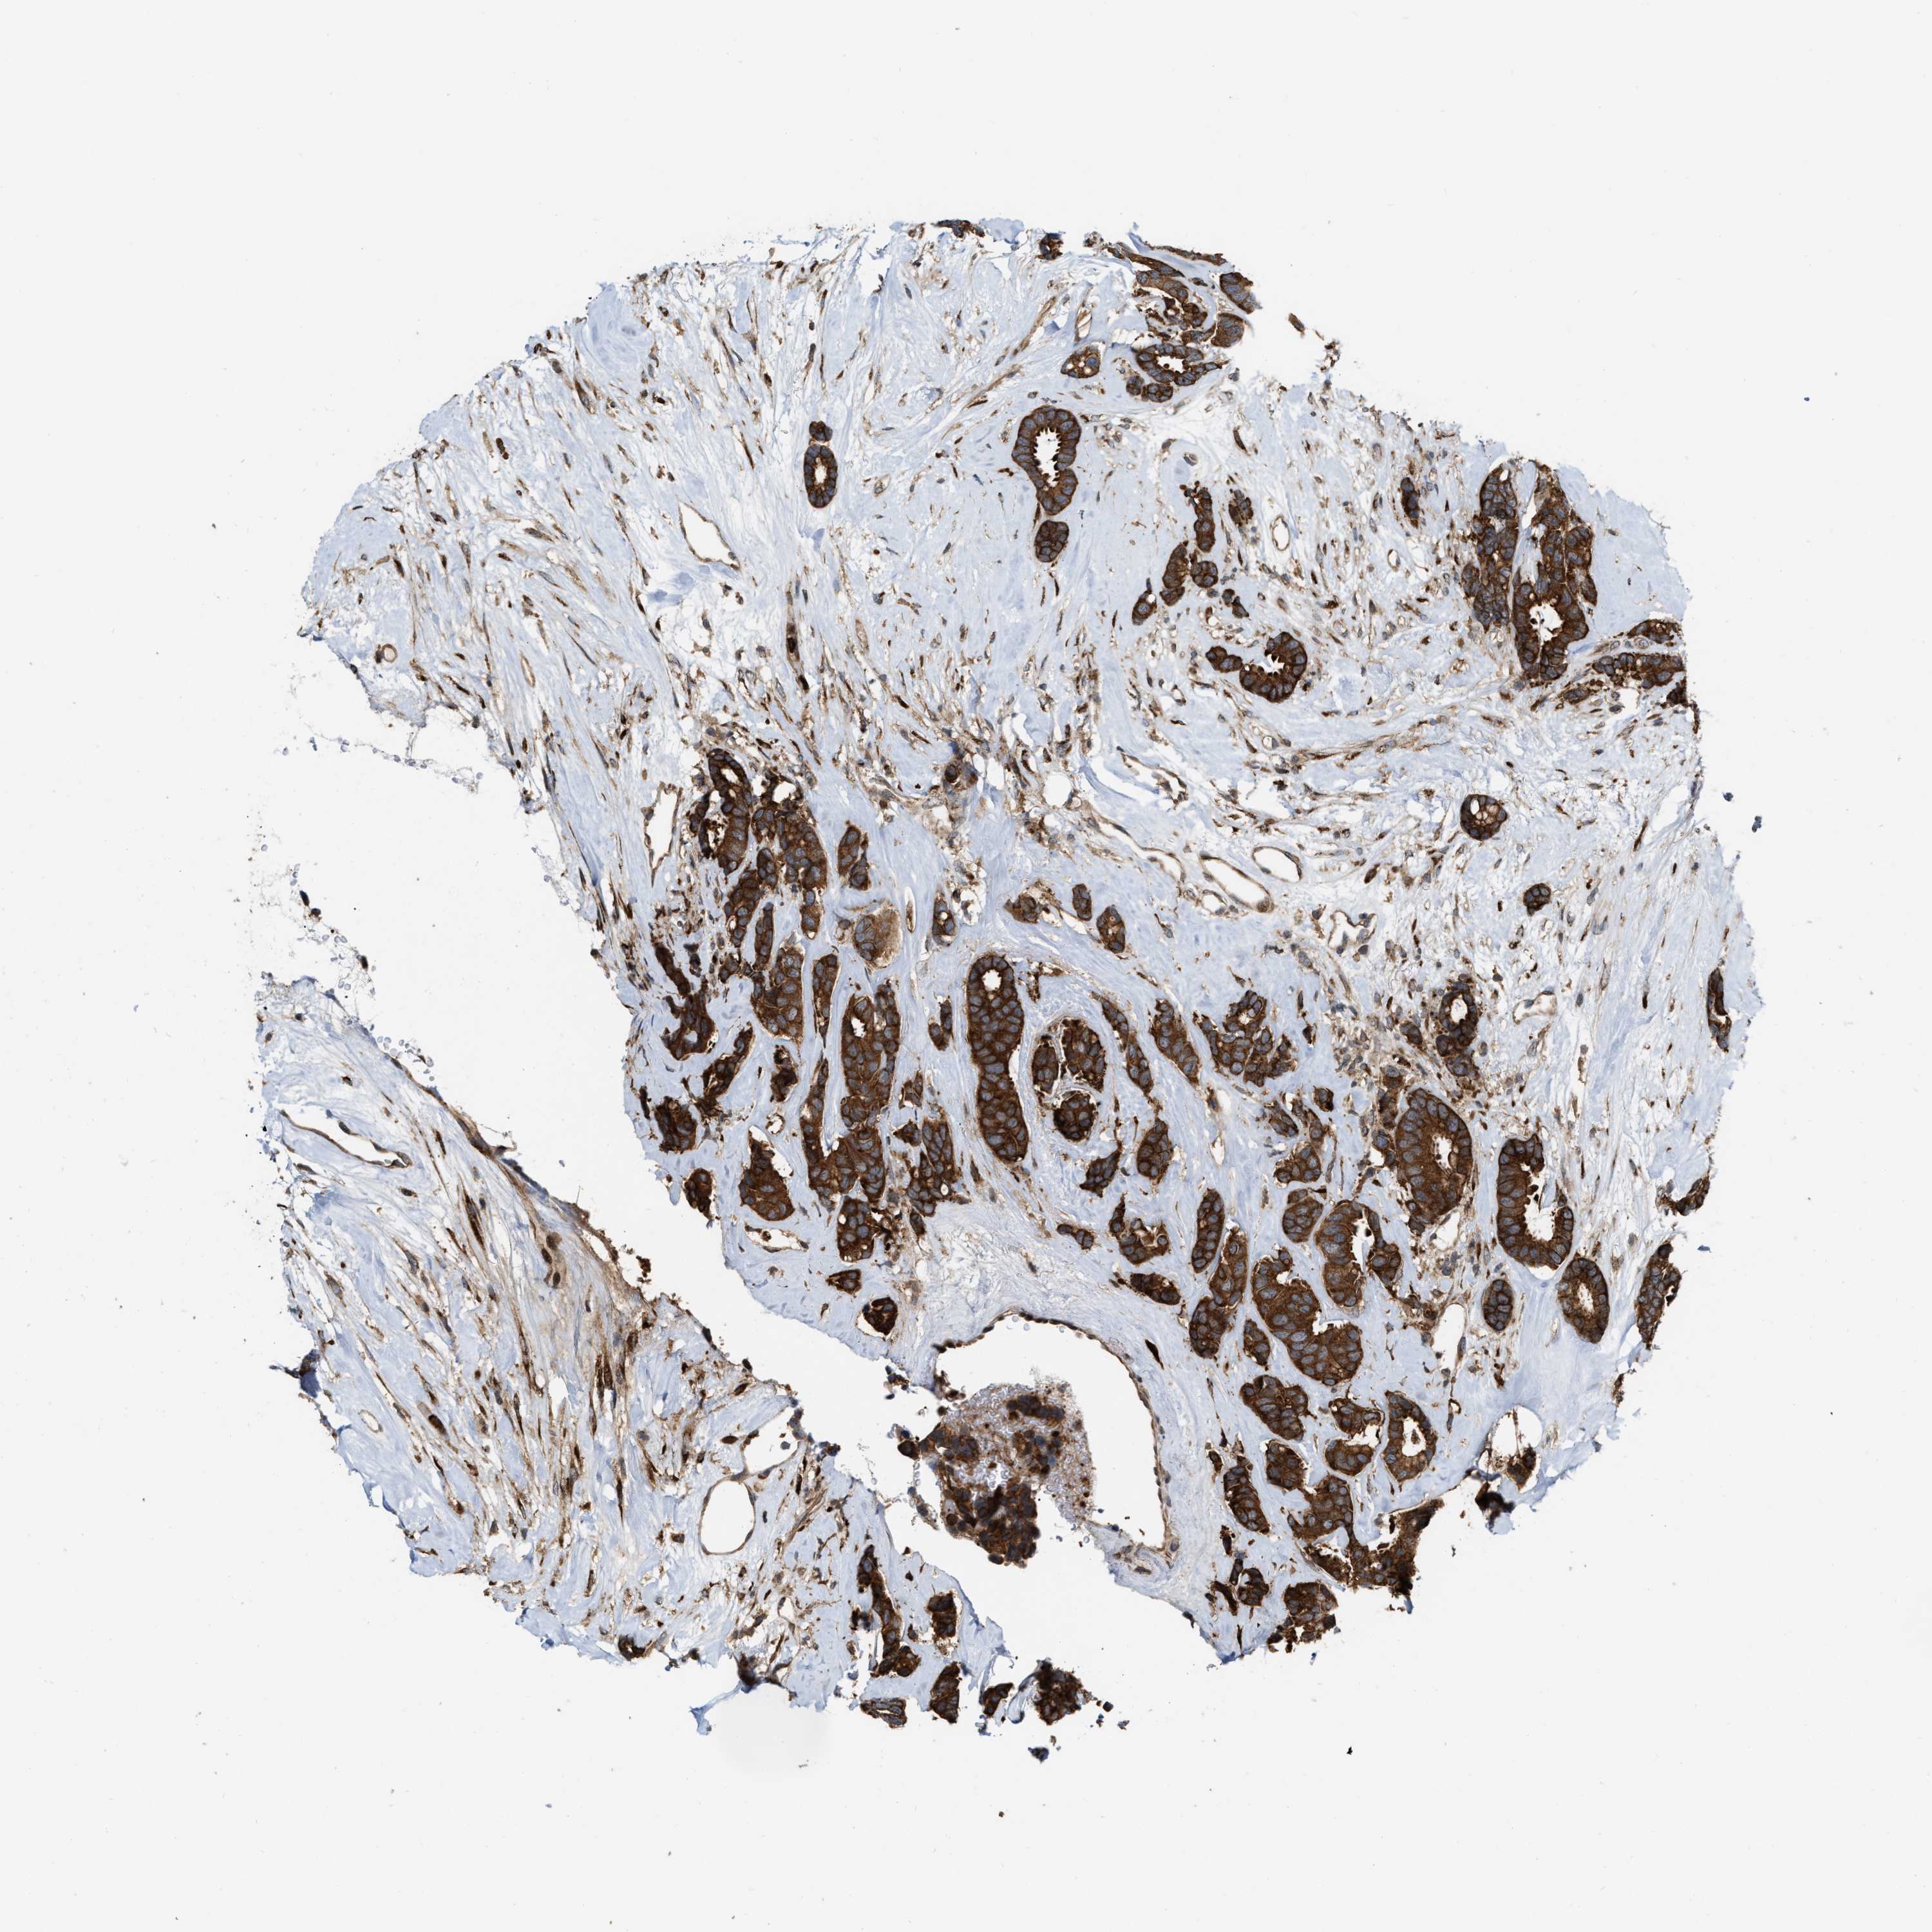

CANCER BREAST CANCER Show tissue menu

BRCA TCGA BRCA VALIDATION PROTEIN EXPRESSION